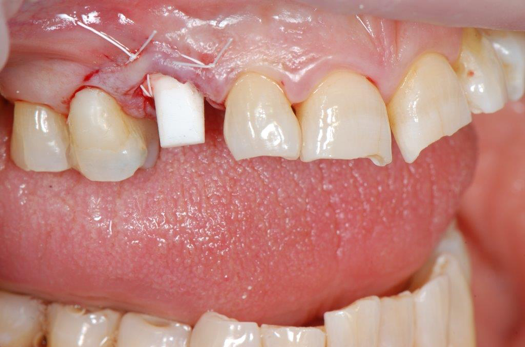

Fig 23. 12 weeks postoperatively.

Figure 23

Figure 23 showed an example of gingival soft tissue creeping occlusally and over the lingual gingival margin of the one-piece ceramic dental implant. This supragingival migration was caused by the exceptional biocompatibility due to the acid-etched surface of the implant, a one-piece implant that prevents bacterial colonization that one may find with two-piece metal-implant systems.